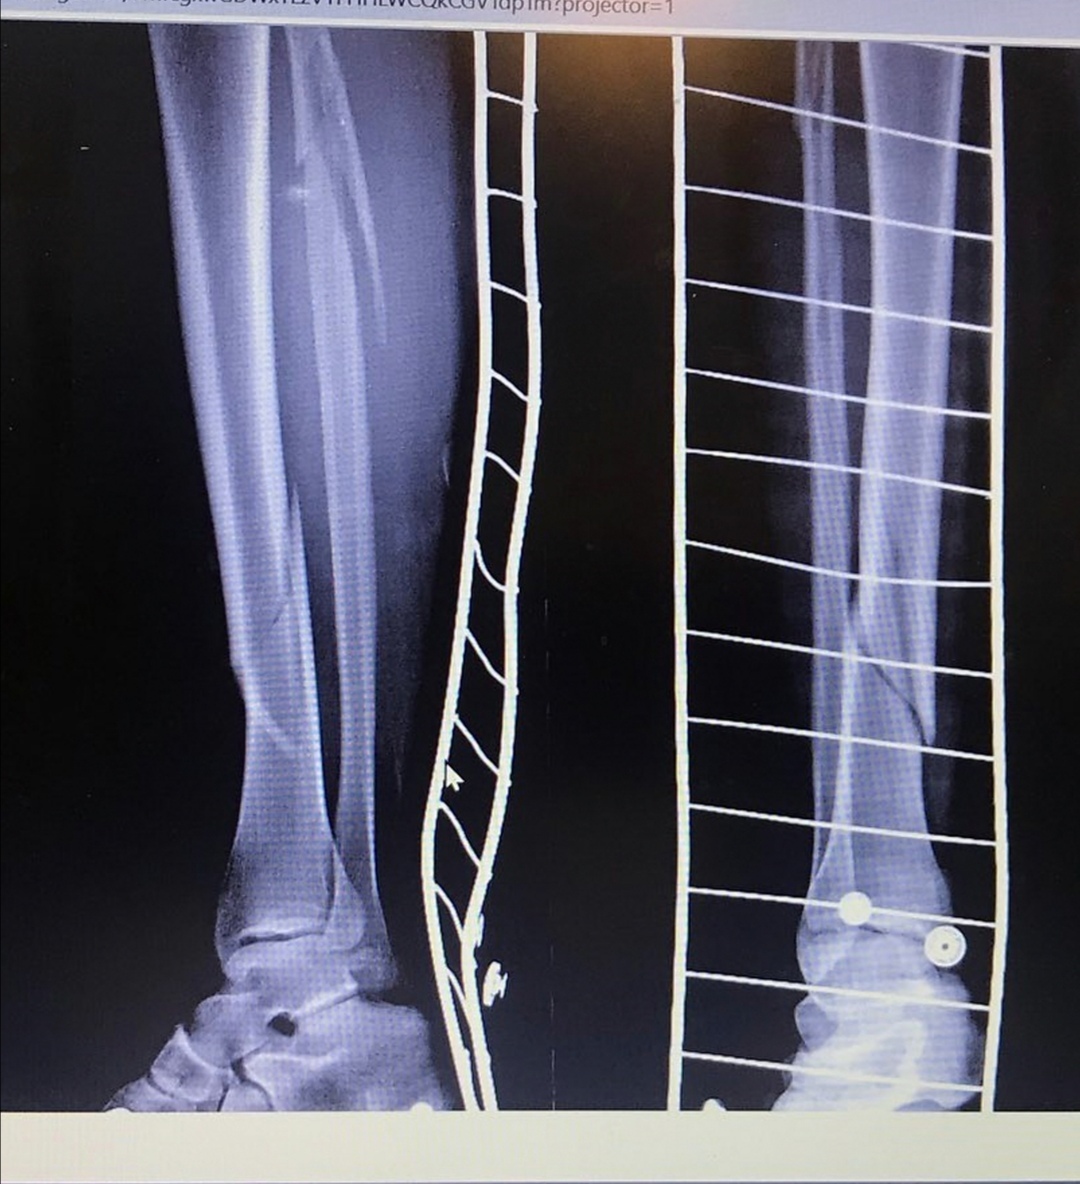

Перелом пилона.... один из самых жопных переломов, которые только можно получить. Он составляет 1% всех переломов нижних конечностей. И это просто развлекаясь на скейтборде. Мне сказали, что будет две операции.... сначала аппарат элизарова , а потом, когда сойдёт опухоль я получу пластины.

В тот же день меня прооперировали. Прикладываю фото, не для слабонервных

Четыре дня я жила с этой штукой на ноге. Боли были сильные.... хотя тогда я ещё не знала, что такое боль. Пару раз приходил физиотерапевт, меня научили ходить на костылях. В общем дни проходили быстро.

Когда железа больше чем костей. Чувствовала себя терминатором.